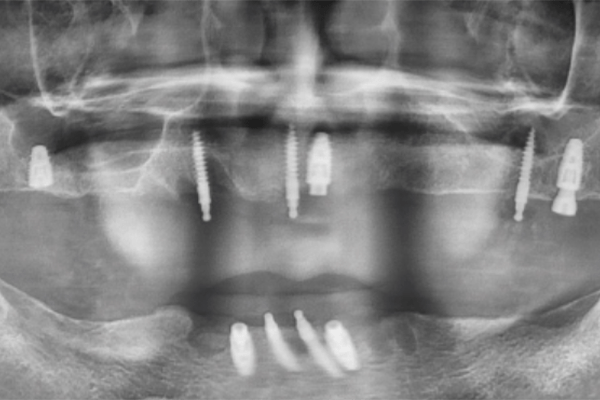

術前X光片(周先生)